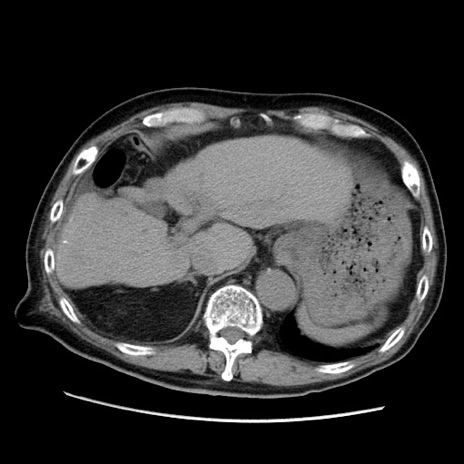

症例21(横断像)

【症例】70歳代男性

【主訴】腹痛

【現病歴】肝硬変・肝細胞癌にてかかりつけの方。約9時間前に食後より腹痛出現。症状が徐々に増悪し、嘔吐出現したため来院。

【既往歴】肝硬変、肝細胞癌(RFA、TACE後)

【身体所見】意識清明、表情苦悶様、BT 36℃、BP 129/78mmHg、P 88bpm、SpO2 97%(RA)、右上腹部から心窩部にかけて圧痛あり、反跳痛なし、筋性防御あり。

【データ】WBC 5800、CRP 0.16